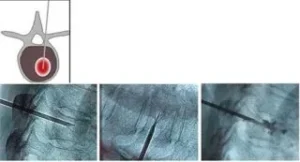

Le fratture vertebrali, se non trattate correttamente, possono portare a gravi complicazioni come dolore cronico, perdita di mobilità, e in alcuni casi, danni permanenti ai nervi. È quindi fondamentale un intervento tempestivo e mirato per ridurre il dolore e favorire la guarigione. I trattamenti per le fratture vertebrali possono includere radiologia interventistica, tecniche minimamente invasive come la vertebroplastica o la kyphoplastica, che permettono di ripristinare la stabilità della vertebra senza ricorrere a interventi chirurgici tradizionali. Queste tecniche vengono eseguite sotto guida radiologica, garantendo alta precisione e riducendo i rischi per il paziente.

In conclusione, le fratture vertebrali sono una condizione comune, che può essere trattata efficacemente con approcci moderni come la radiologia interventistica, che offre un’alternativa sicura ed efficace rispetto alle tradizionali chirurgie invasive. Se sospetti di avere una frattura vertebrale o hai una condizione di salute che aumenta il rischio di fratture, è importante consultare un medico specialista per un’accurata valutazione e per discutere le opzioni di trattamento più adatte.